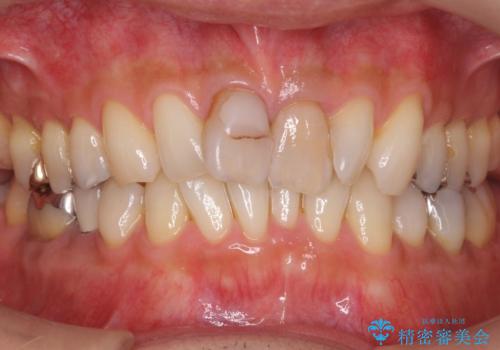

- 銀歯をすべてやり替えたいとのことで来院された患者様です。

再根管治療が必要なところは再根管治療から、そうでないところは補綴物のみをやり替えていくこととなりました。

銀歯のやり替えと並行してホワイトニングも行いました。

結果的には銀歯がすべて白くなり、前歯のガタつきもある程度改善され大変喜んでいただけました。